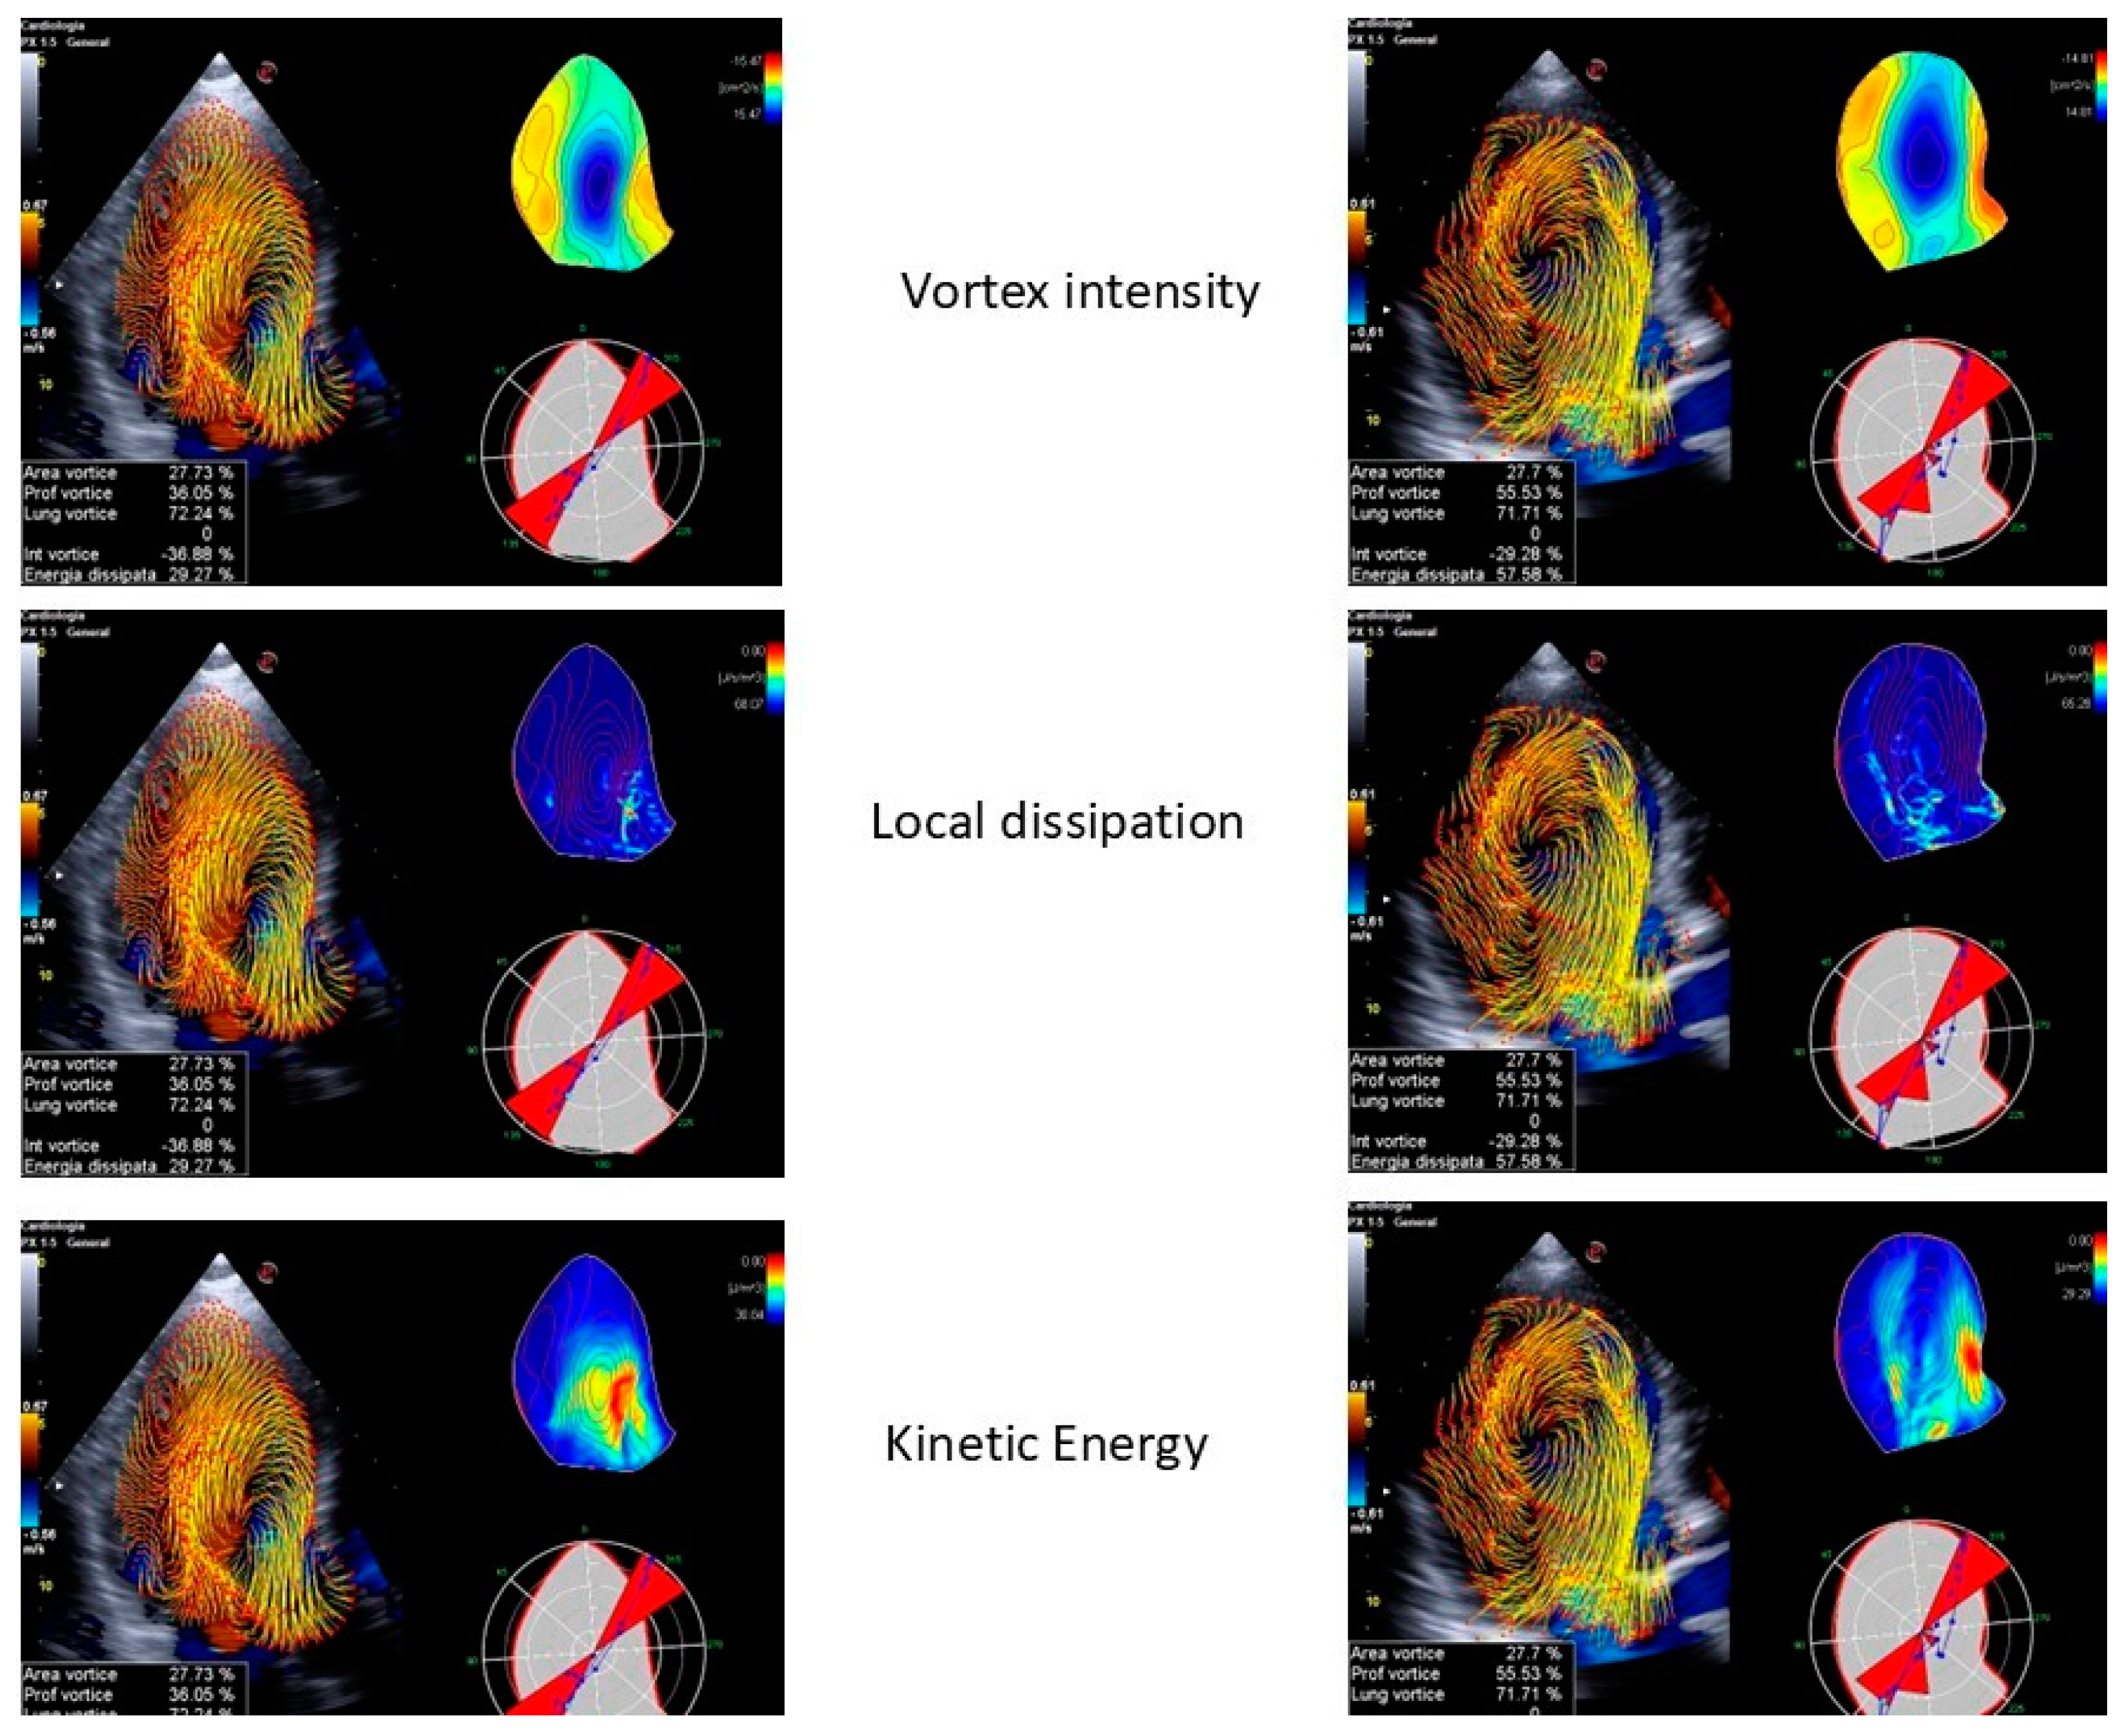

- LV function: Vortex imaging helps clinicians visualize and measure the vortices within the LV, which are crucial for the efficient blood ejection and filling. By analyzing these flow patterns, clinicians can identify early signs of LV dysfunction that might not be obvious using standard measures. Two vortex components were consistently observed following each transmitral filling wave. The anterior vortex was analyzed due to its greater relevance in the cardiac cycle, occurring after early filling and atrial contraction. The vortex generated after early filling appears to aid LV inflow and plays a more prominent role in individuals with impaired relaxation. The vortex formed after atrial contraction seems to store kinetic energy and redirect the flow toward the outflow tract, facilitating ejection and contributing to the mitral valve closure [56]. Diastolic vortices are especially important for assessing the left atrial function and ventricular filling pressures. This is particularly valuable in conditions like heart failure with a preserved ejection fraction, where vortex dynamics can reveal underlying diastolic dysfunction [56]. Moreover, a reduced vortex formation time (VFT), a dimensionless index used to quantify the vortex development, strongly correlates with LV dysfunction and predicts adverse outcomes in patients with HF [57]. As an example, the VFT ranged between 3.3 and 5.5 in healthy subjects, but decreased to values < 2.0 in patients with dilated cardiomyopathy [58].

- Valve disease: In mitral regurgitation, vortex imaging can depict the altered flow patterns caused by the regurgitant jet, helping to quantify the severity of the lesion and its effect on the LV filling. Restoring normal intracardiac LV flow patterns, as observed primarily after mitral valve replacements, may help preserve kinetic energy momentum, thereby reducing the LV workload and shear stress. A recent study revealed that intracardiac blood flow patterns are restored after mitral valve repairs, regardless of the repair technique used. In contrast, a mitral valve replacement with either biological or mechanical prostheses in non-anatomical orientations is associated with persistent alterations in the blood flow. A transcatheter edge-to-edge repair completely disrupts the LV vortices, while a transcatheter mitral valve replacement with a Tendyne valve has an effect similar to a mitral valve repair in restoring normal flow patterns [59]. Similarly, in aortic stenosis, the technique can illustrate the turbulent flow distal to the stenotic valve, offering a visual representation of the hemodynamic burden on the LV (Figure 5 and Figure 6). This information aids in the decision-making process for valve repairs or replacements by providing a more nuanced understanding of the disease’s impact on cardiac function [60,61]. Some studies have reported that aortic stenosis is associated with reduced LV filling efficiency, resulting in decreased VFT values. However, in patients with aortic stenosis and moderate aortic insufficiency, the VFT significantly increases, suggesting that the VFT may be an unreliable index of LV filling efficiency when competitive diastolic flows into the LV are present [62].

- Congenital heart diseases: CHDs often involve complex intracardiac flow abnormalities that can be challenging to assess with traditional imaging techniques. Vortex imaging is particularly effective in this area, providing a detailed visualization of abnormal flow patterns, which is essential for accurate diagnosis and surgical planning. For instance, in conditions such as the Tetralogy of Fallot or the transposition of the great arteries, vortex imaging can depict the intricate flow dynamics and help in understanding the physiological consequences of the defects. In patients with transposition of the great arteries, an increased flow across the pulmonary valve secondary to a large ventricular septal defect may be responsible for a Doppler gradient at the level of the pulmonary valve, mimicking a pulmonary stenosis. In this case, the differentiation between a real valvular stenosis and a gradient secondary to volume overload is extremely important in defining the surgical timing and the type of surgery (arterial switch and ventricular septal defect closure vs. Rastelli operation). These are the kinds of situations where the traditional Doppler and color Doppler techniques demonstrate all their limitations. The use of blood speckle imaging to study flow dynamics has proven to be helpful in formulating the correct diagnosis, especially in this difficult context [63]. Post-surgical follow-ups in CHD patients also benefit from vortex imaging, as it can monitor the restoration or alteration of normal flow patterns [60].

- LV dyssynchrony: Vortex imaging can assess the changes in intracavitary flow patterns before and after the CRT implantation, providing insights into the therapy’s effectiveness. Goliasch et al. utilized vortex imaging to assess the impact of an acute interruption and reactivation of the CRT. Deactivating the CRT significantly disrupted the LV filling, resulting in the reduced mitral inflow acceleration and increased total diastolic volume. This, in turn, led to the formation of an underdeveloped diastolic vortex, which impaired the transfer of kinetic energy from diastole to systole, delayed the redirection of the blood flow toward the aorta, and hindered the timely opening of the aortic valve, thereby prolonging the isovolumetric contraction period [64]. Upon the reactivation of the CRT, the LV filling improved immediately, and the total diastolic volume decreased. This restored the optimal timing of the diastolic vortex formation and shortened the isovolumetric interval [64]. By visualizing the improvement in flow efficiency and the reduction in dysfunctional vortices, clinicians can better evaluate the success of a CRT and make adjustments as needed to optimize patient outcomes.

- Cardiomyopathies: In DCM, vortex imaging helps to evaluate the impact of dilated chambers on intracardiac flow and to pinpoint the regions of flow stagnation that may contribute to thrombus formation. Furthermore, vortex patterns are used to gauge the severity of HF, as fragmented or abnormal patterns are associated with increased cardiac dysfunction [65].